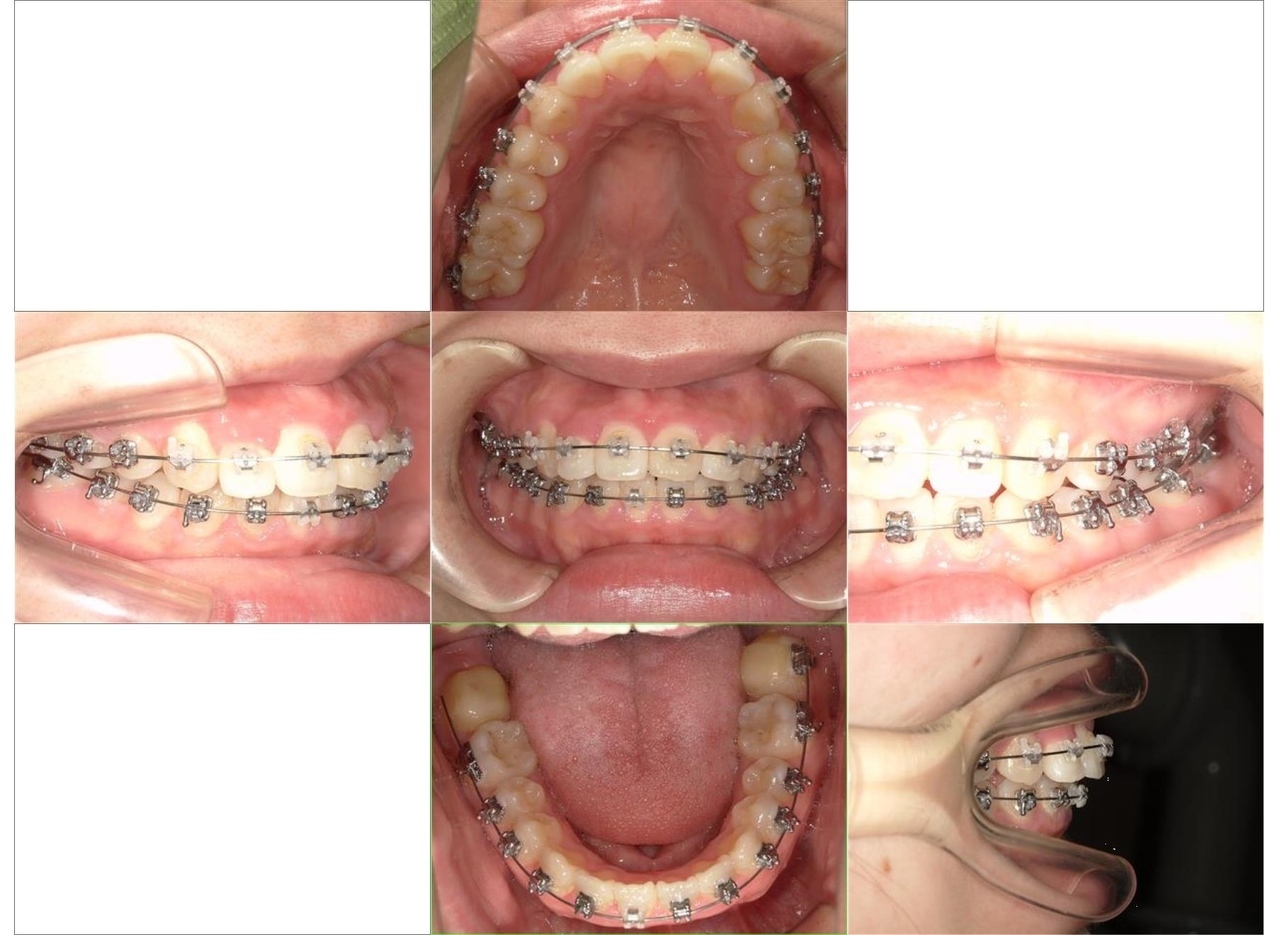

はじめに、乳歯の抜歯を行い、乳歯を抜歯したスペースに永久歯を配列しました。また、舌側に位置していた永久歯も上顎の歯列に配列しました。全体の歯の配列が整ってきたので、顎間ゴムにて咬合の緊密化を行い、矯正治療を終了しました

マルチブラケット装置による矯正治療は、歯の三次元的な動きが可能であることから、歯科矯正治療においては、とても効果の高い治療法であると考えています。